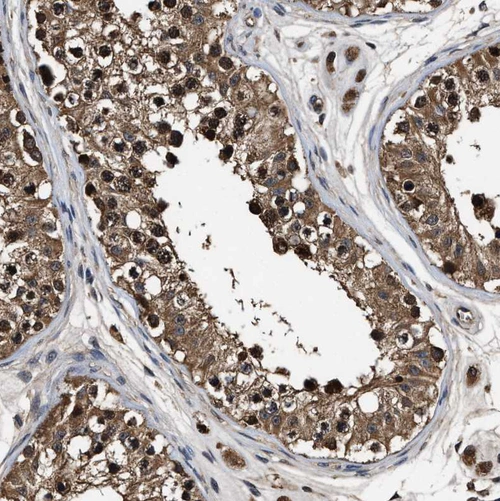

Immunohistochemical staining of human testis shows strong cytoplasmic and nuclear positivity in cells in seminiferous ducts.